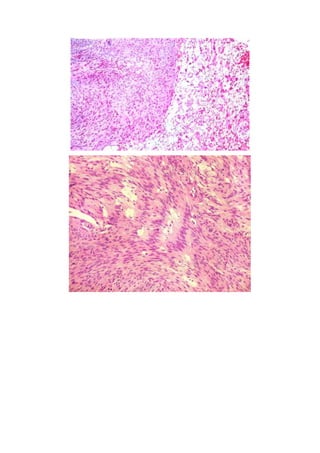

Este documento describe los diferentes tipos de vértigo, incluyendo causas centrales y periféricas, y explica cómo la duración puede indicar la etiología. Luego se enfoca en el schwannoma acústico, un tumor benigno del nervio vestibulococlear que representa el 8-10% de los tumores intracraneales en adultos y se origina en la porción vestibular del nervio. Los síntomas incluyen deterioro auditivo, tinnitus, pérdida de equilibrio, entumecimiento facial y debilidad muscular parcial.